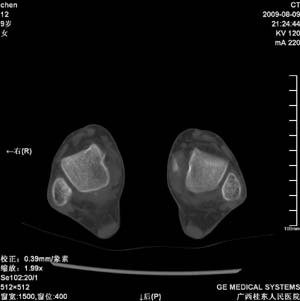

标题: PED2867:右侧内踝肿胀,骨质改变,请各位老师会诊 [打印本页]

标题: PED2867:右侧内踝肿胀,骨质改变,请各位老师会诊

九岁小朋友,近期左侧内踝疼痛,局部肿胀,平时无特殊,近期经常溜干冰

对不起,是右侧内踝肿胀

双踝关节骨质及发育未见异常。

左侧内踝密度增高,请结合临床!